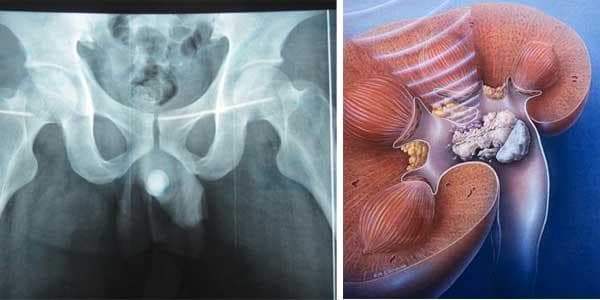

Hình ảnh một bệnh nhân bị sỏi niệu đạo